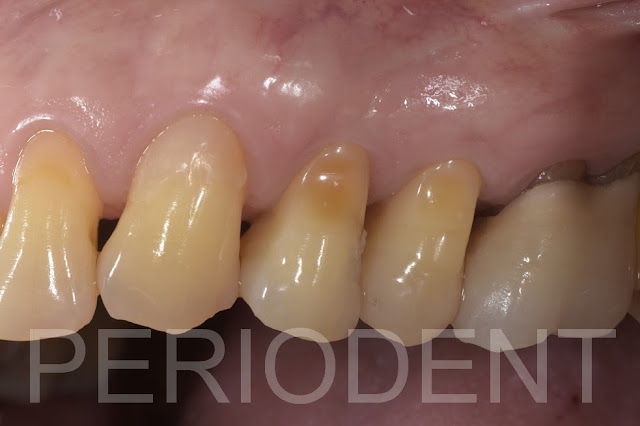

患者第一小臼齒遠心蛀牙

一星期拆線時

一個月檢查

二個月時